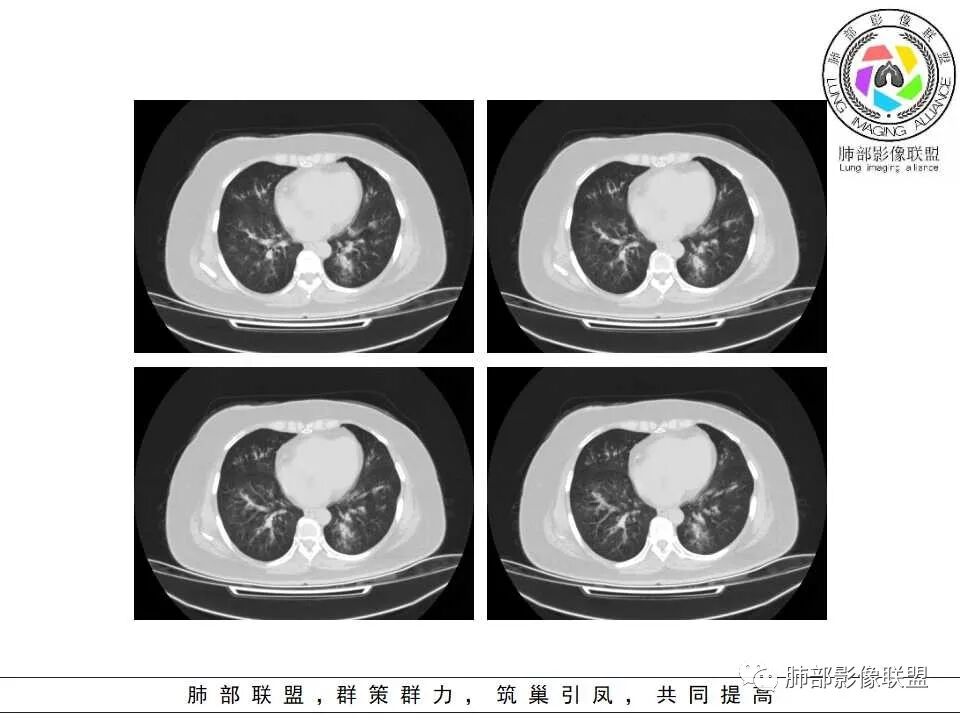

影像上是否有肺出血呀?感觉肺动脉周围有渗出,气道曲霉然后血管侵犯入血?

老年女性,发现白细胞升高两年,此次入院多次查外周血白细胞>30*10^9/L,淋巴降低,CRP显著升高,但病程中无发热,以细菌性炎不好解释;CT提示有脾大,结合外周血象,首先考虑存在血液系统疾病(白血病)基础,且未系统诊治;肺部CT提示双肺中轴间质增粗,伴随支气管管壁增厚?多发树丫及腺泡结节,部分呈点晕征,可见肺动脉分枝增粗,一元论考虑白血病肺部浸润;二院论考虑白血病并发气道侵袭曲霉。以患者病程进展看,更倾向于白血病肺部浸润。

肺动脉高压:性质待查,血象哪位老师解释一下,看右上支气管,怀疑以前都有过

1.病灶沿支气管分布的特点相当明显,相应支气管壁广泛增厚。这种与支气管关系极为密切的片影和/或结节影,常高度提示气道相关感染,如支气管肺炎。

2.患者两肺多发病变,具有广泛性。如此广泛分布更多见于免疫低下的机会性感染。

3.支气管壁广泛增厚对气道侵袭性曲霉病具有一定的提示意义。注意患者没有支气管扩张,临床也未提供IGE等实验室资料。

二.血管侵袭性肺曲霉病

1.多见于血液恶性肿瘤及造血干细胞移植患者。两肺多发,多见磨玻璃晕,有时病灶基底贴近胸壁形成楔形影。

2.很少支气管壁增厚,也无支气管扩张,少见树芽征。